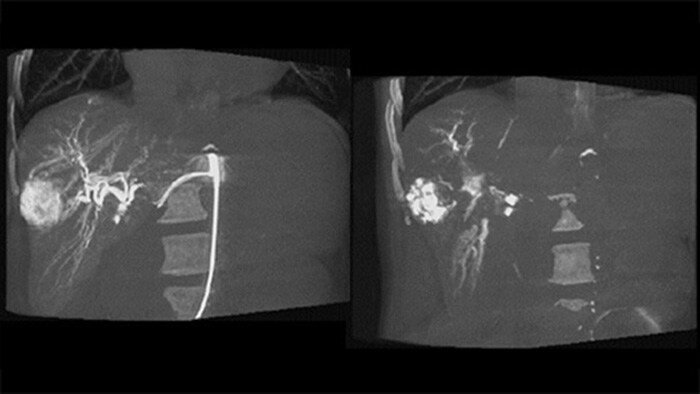

Chemo-/Radioembolisationsverfahren wie TACE und SIRT erfordern eine höhere Standardisierung und Effizienz. Die Tumore müssen jedes Mal zuverlässig und konsistent lokalisiert, alle Versorgungsgefäße erkannt und die geeigneten interventionellen Maßnahmen geplant und durchgeführt werden. Unsere dedizierte Lösung kann die Erkennung von Versorgungsgefäßen im Vergleich zur alleinigen Verwendung von Cone-Beam-CT signifikant verbessern. Für möglichst effiziente TACE-Verfahren kann EmboGuide die Empfindlichkeit verbessern, falsch positive Ergebnisse reduzieren und eine höhere Konsistenz zwischen den befundenden Medizinern gewährleisten.1

Unsere dedizierte Lösung verbessert die Erkennung von Versorgungsgefäßen signifikant. Mit EmboGuide können Sie die Effizienz Ihrer TACE-Verfahren maximieren, da die Funktion die Empfindlichkeit verbessert, falsch positive Ergebnisse reduziert und eine höhere Konsistenz zwischen den befundenden Medizinern ermöglicht.1 Darüber hinaus bietet EmboGuide eine Arbeitsablauf-basierte Live-3D-Führung mit automatischer Erkennung der Versorgungsgefäße1.

CBCT Dual ermöglicht die 3D-Erfassung einer arteriellen Phase zur Darstellung von Gefäßstrukturen und einer postarteriellen Phase zur Darstellung der Ansammlung von Kontrastmittel in einem automatisierten Schritt.5

Dual View ermöglicht die gleichzeitige Darstellung von zwei CBCT-Datensätzen. Sowohl die arterielle als auch die postarterielle Phase können nebeneinander oder in einer fusionierten Überlagerungsansicht angezeigt werden.

Die Erfassung eines 3D-Bildes nach der Embolisation ermöglicht die Darstellung von gezielt eingebrachtem embolischem Material wie Lipiodol oder röntgenpositiven Partikeln im Tumor.5

Dual View ermöglicht die gleichzeitige Darstellung eines 3D-Bildes der arteriellen Phase vor der Embolisation und eines Bildes nach der Embolisation zur Bestimmung des Behandlungsendpunkts.